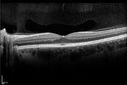

Papilledema - Spectral Domain OCT used for Diagnosis - 14 year old Child - Line Scan over Nerve Shows Retinal Edema1737 views14-year-old was with optic nerve swelling asymptomatic - picked up during routine eye exam. OD 20/20, OS 20/32

SD-OCT is used to differentiate optic disc edema from optic nerve head drusen (which are not yet calcified in children).

Papilledema - Spectral Domain OCT used for Diagnosis - 14 year old Child - Nerve Fiber Layer Scan shows swelling1647 views14-year-old was with optic nerve swelling asymptomatic - picked up during routine eye exam. OD 20/20, OS 20/32

Papilledema - Spectral Domain OCT used for Diagnosis - 14 year old Child - Line Scan over Nerve Shows Retinal Edema1616 views14-year-old was with optic nerve swelling asymptomatic - picked up during routine eye exam. OD 20/20, OS 20/32